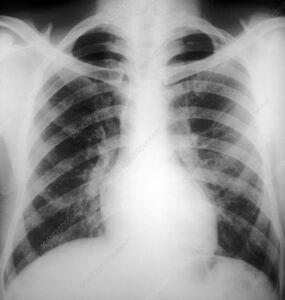

Pneumonia is an infection that inflames the air sacs in one or both lungs. निमोनिया एक संक्रमण है जो एक या दोनों फेफड़ों में हवा की थैली को फुला देता है। The air sacs may fill with fluid or pus (purulent material), causing cough with phlegm or pus, fever, chills, and difficulty breathing. हवा की थैलियां द्रव या मवाद (प्यूरुलेंट सामग्री) से भर सकती हैं, जिससे कफ या मवाद के साथ खांसी, बुखार, ठंड लगना और सांस लेने में कठिनाई हो सकती है।